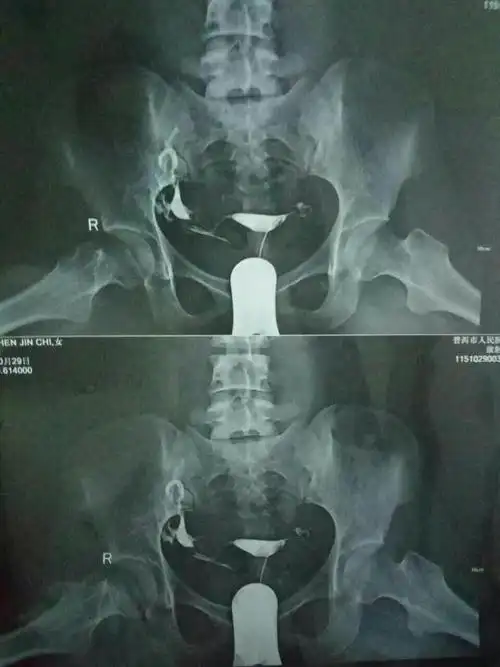

输卵管堵塞这样做通水能完全通吗能顺利怀孕吗.求回答